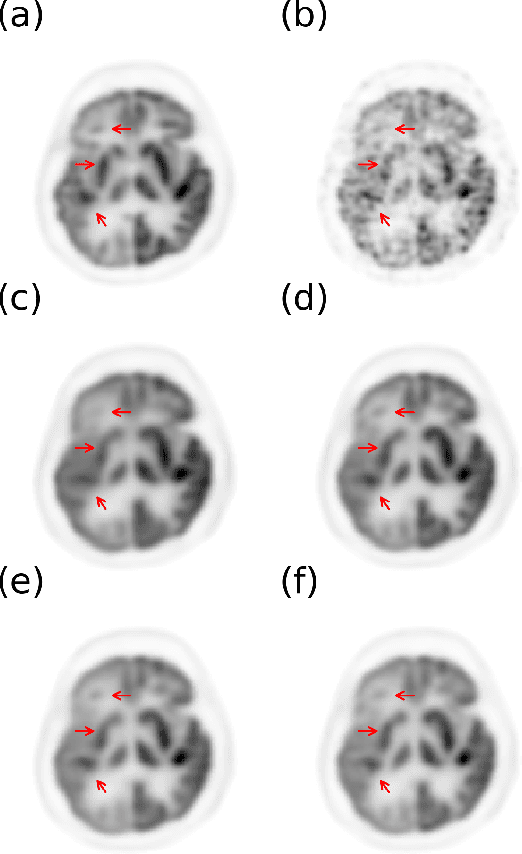

Abstract:Positron emission tomography (PET) is widely used in various clinical applications, including cancer diagnosis, heart disease and neuro disorders. The use of radioactive tracer in PET imaging raises concerns due to the risk of radiation exposure. To minimize this potential risk in PET imaging, efforts have been made to reduce the amount of radio-tracer usage. However, lowing dose results in low Signal-to-Noise-Ratio (SNR) and loss of information, both of which will heavily affect clinical diagnosis. Besides, the ill-conditioning of low-dose PET image reconstruction makes it a difficult problem for iterative reconstruction algorithms. Previous methods proposed are typically complicated and slow, yet still cannot yield satisfactory results at significantly low dose. Here, we propose a deep learning method to resolve this issue with an encoder-decoder residual deep network with concatenate skip connections. Experiments shows the proposed method can reconstruct low-dose PET image to a standard-dose quality with only two-hundredth dose. Different cost functions for training model are explored. Multi-slice input strategy is introduced to provide the network with more structural information and make it more robust to noise. Evaluation on ultra-low-dose clinical data shows that the proposed method can achieve better result than the state-of-the-art methods and reconstruct images with comparable quality using only 0.5% of the original regular dose.